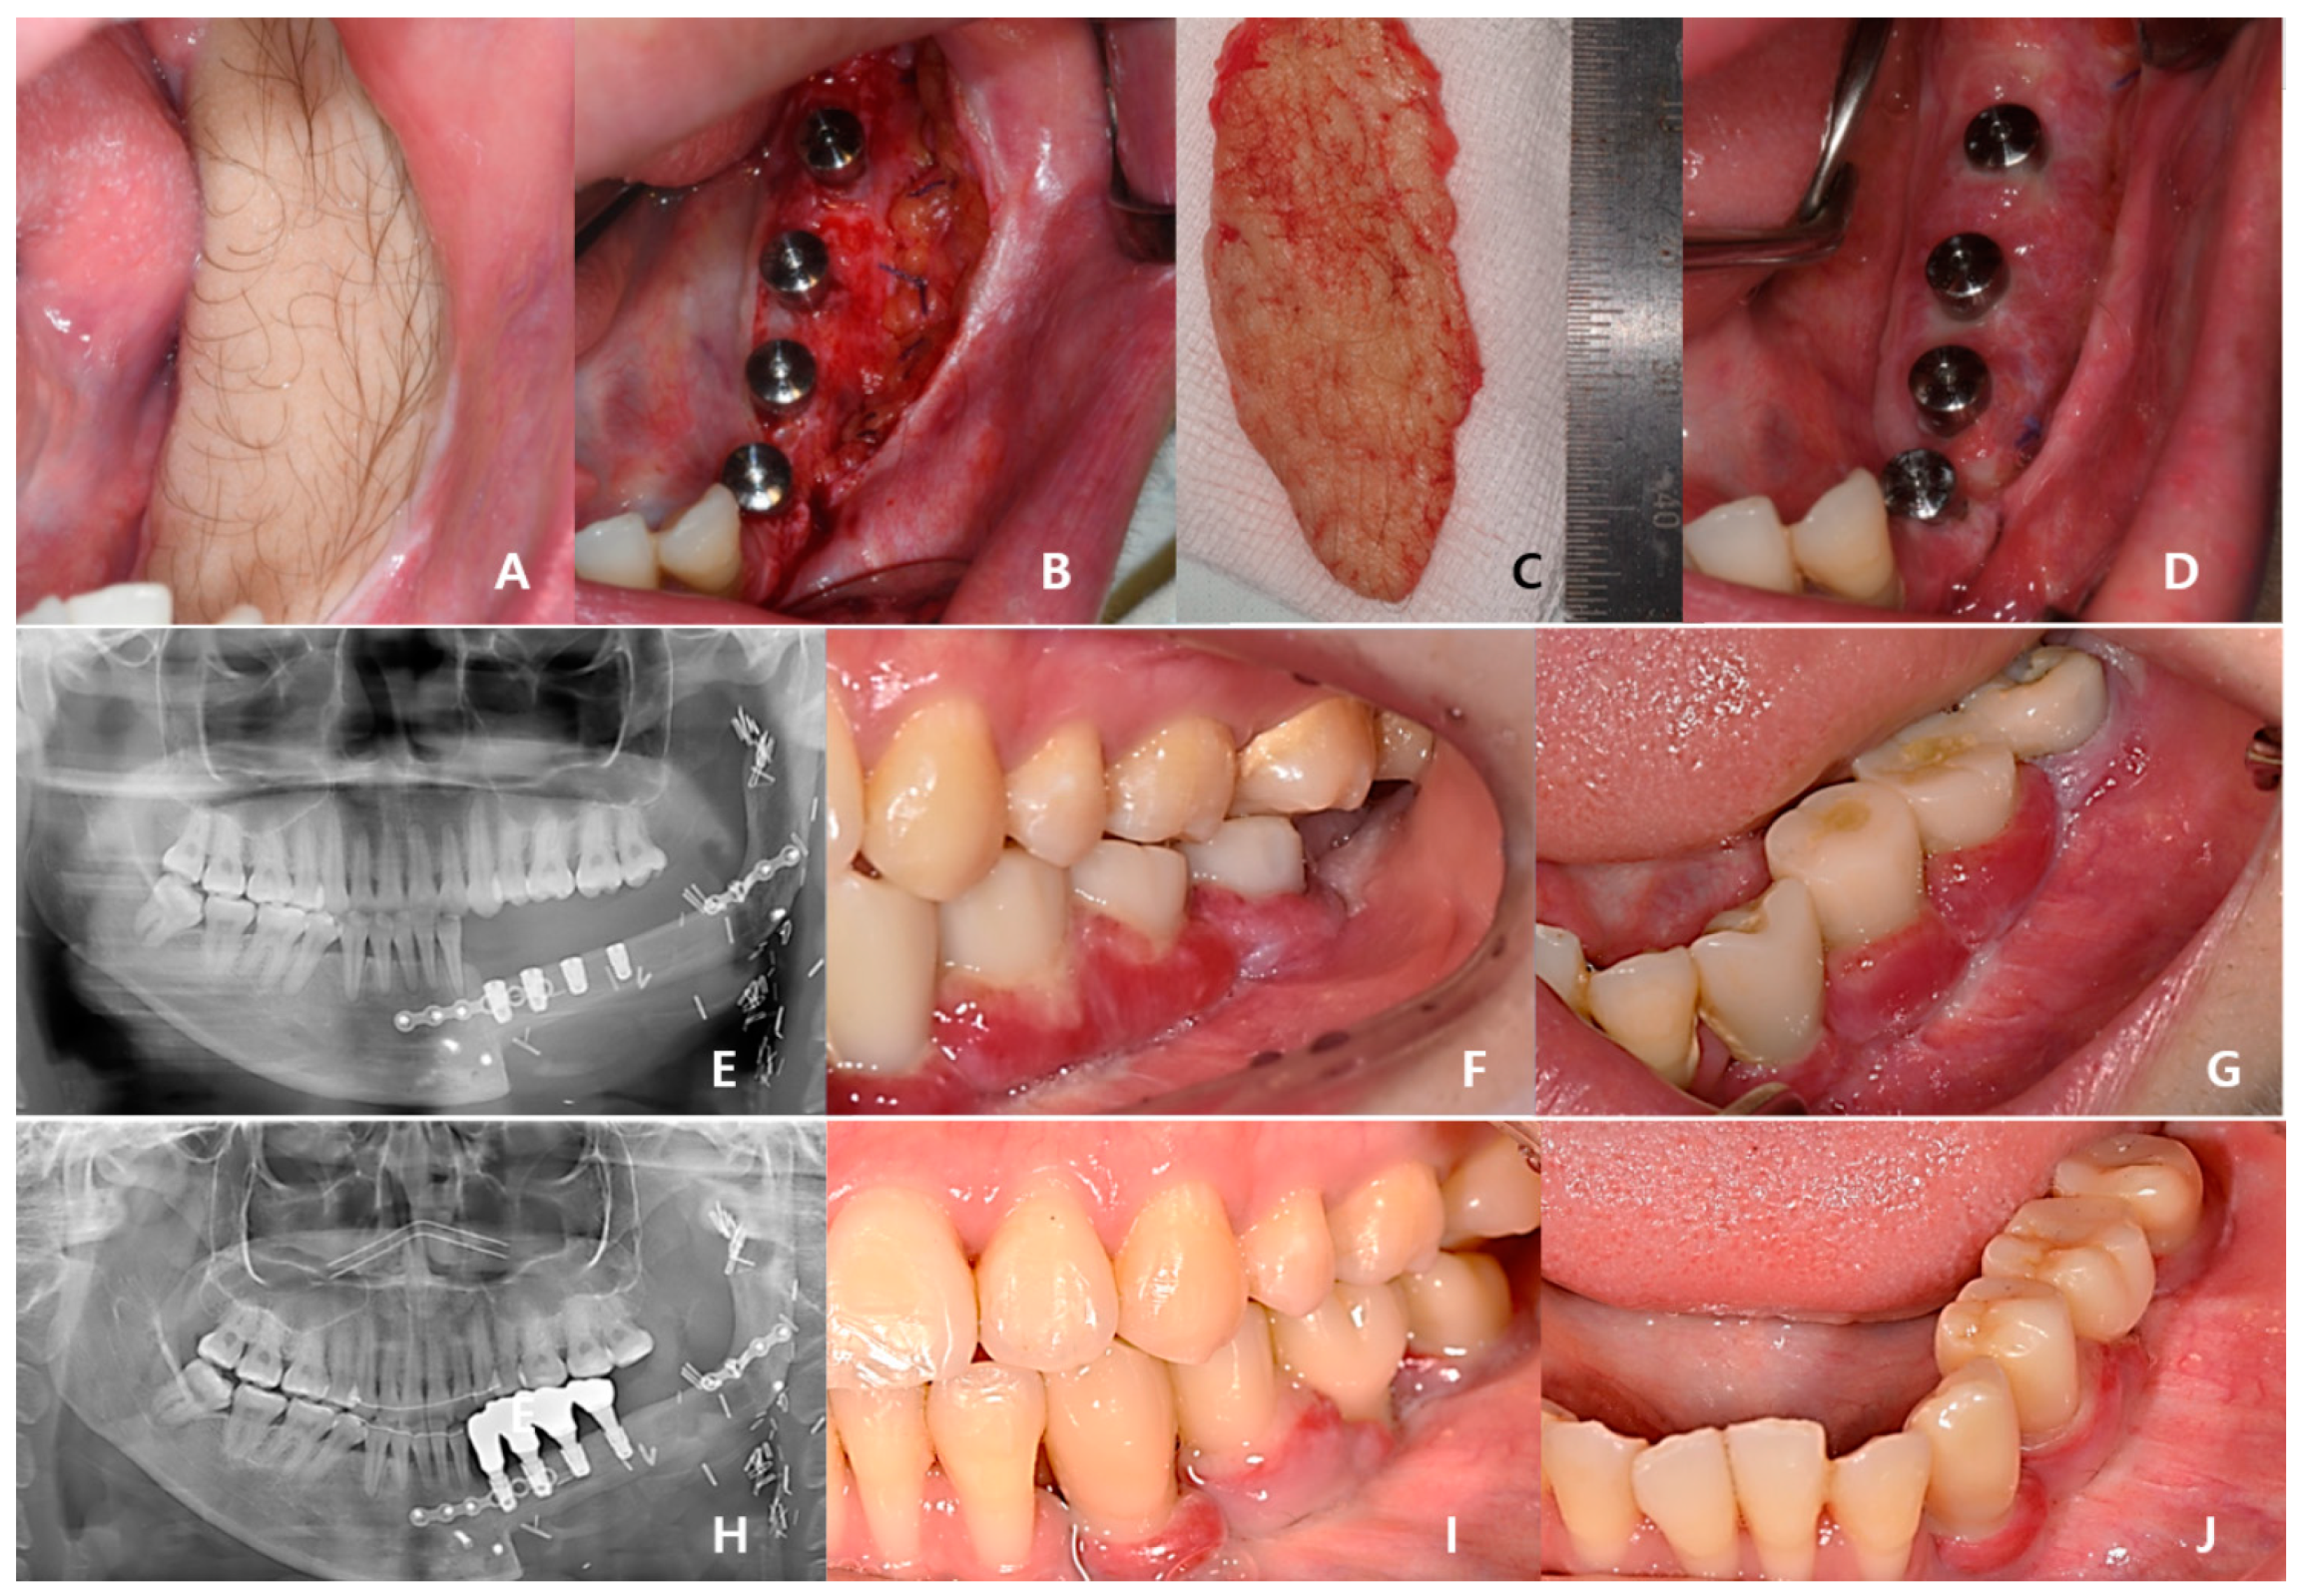

Three years after cancer surgery, 2-stage dental implant (TS-III CA; Osstem Implant Co., Busan, Republic of Korea) installation was performed outpatiently under local anesthesia, the final implant prosthesis was completed 4 years after surgery, and the patient recovered functionally and aesthetically (Figure 8).

Figure 8. In total, 40 months after cancer surgery, the secondary implant surgery was performed, and the surrounding mucosa was sutured to the periosteum of the fibula to form an attached gingiva: (A) preoperative intraoral photo with hairy fibular skin; (B) postoperative intraoral photo; (C) removed fibular skin; (D) stich-out after 2 weeks; (E) panoramic view immediately after dental implant 1st surgery; (F,G) temporary prosthesis after 4 months; (HJ) Recovery of masticatory function was completed without inflammation after delivery of the final prosthesis 4 years after cancer surgery.